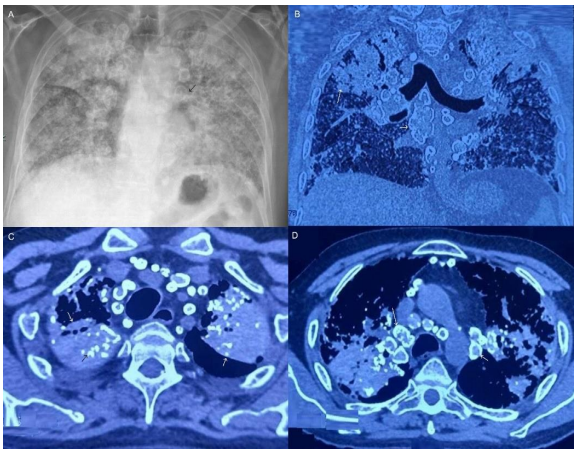

A man in his late fifties presented to us with dry cough and gradually progressive shortness of breath for 5 years, with breathlessness at rest for the last 6 months. There was no history of fever, chest pain, hemoptysis, loss of appetite, weight or connective tissue disease features. He has not been working for the last 5 years before which he worked in a cast making factory for 20 years with history of silica exposure. There was pandigital grade 3 clubbing. Chest auscultation revealed bilateral diffuse fine inspiratory crepitations. His chest radiograph showed bilateral diffuse non homogenous opacities with upper zone predominance, bilateral volume loss, mediastinal and hilar calcifications (Panel A). We performed contrast enhanced computed tomography (CECT) chest which revealed bilateral upper lobe dense fibrotic lesions representing progressive massive fibrosis, with areas of cavitation and calcification within. In addition, bilateral diffuse nodular opacities, mediastinal and hilar lymph node calcifications were seen (Panel B, C, D). The pattern of calcification was the classical ‘eggshell calcification’, with a calcified rim around the periphery of the lymph nodes.

All the features descibed by Jacobson et al were present in our case. The diagnosis of chronic silicosis was made on clinicoradiologic basis in conjunction with a conducive occupational history. His spirometry showed severe restriction. Associated pulmonary tuberculosis, systemic sclerosis or lung malignancy was ruled out. We notified the occupational safety department. He was evaluated and added to the prospective lung transplant candidate list.

Figure 1